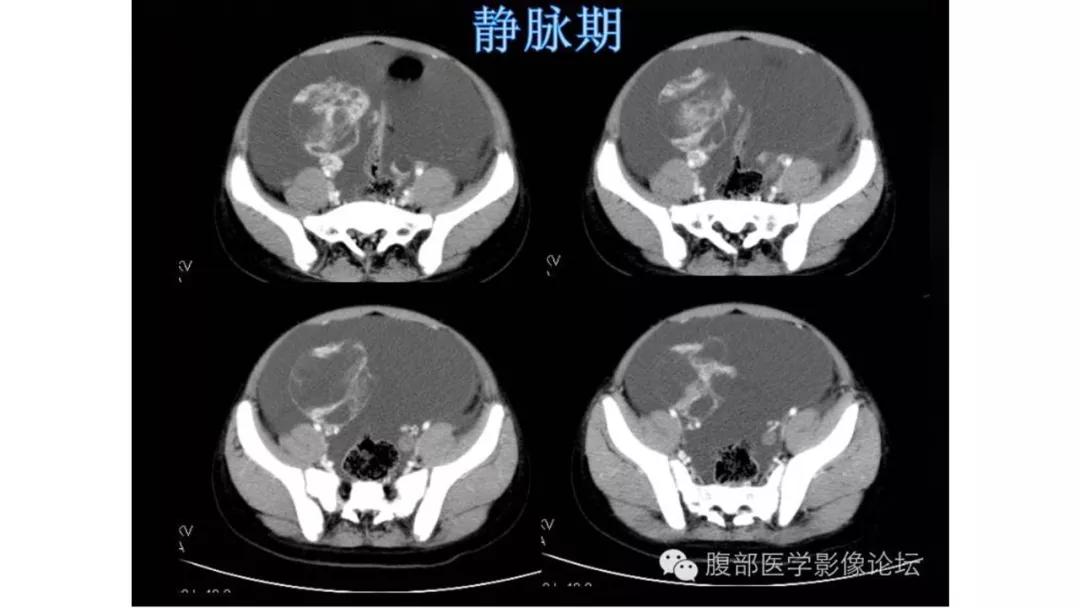

上皮性肿瘤:最常见,恶性多(卵巢癌),良性少。好发于50Y以上,发现时多为中晚期。多呈囊性或以囊性为主的囊实性肿块,完全实性者少见。形态多数不规则,边界模糊,囊壁及房间隔常不规则增厚,菜花样肿物或壁结节,囊实性区域分界不清,实性肿瘤常有不规则低密度或坏死区,可有边界模糊沙粒状或块状钙化,中-高度强化。良性者边界清晰,囊壁薄光整,无壁结节,实性部分呈无或轻度强化。

恶性者常呈实性或混杂性肿块,多数边界清楚,可伴有不规则沙粒状钙化。无性细胞瘤常为实性肿块,轻度强化,内胚窦瘤实性成分明显强化,不成熟畸胎瘤呈混杂密度。结合年龄及临床生化检查,有助于诊断。

- 良性及低恶肿瘤强化往往比较轻度,高恶肿瘤强化往往比较快而明显,也就是说,迅速、明显强化的卵巢肿瘤往往代表高度恶性